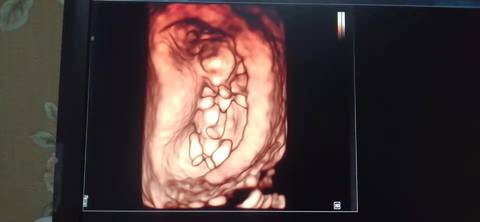

十二周的nt,是不是小棉袄啊? 医生给看宝宝腿的时候生殖器那里是平平的,是女宝吗?我和老公都挺想要小棉袄的

journal_insert_pic_1741079492journal_insert_pic_1741080010journal_insert_pic_1741080172journal_insert_pic_1741080318

亲亲,我们都是一样觉得好奇,没什么依据的呢,就留个惊喜给自己吧,一切如愿!

你好,我们是看不出来的,只要是健康的宝宝,都是上帝赐予的礼物,孕期定期检查,祝心想事成 。